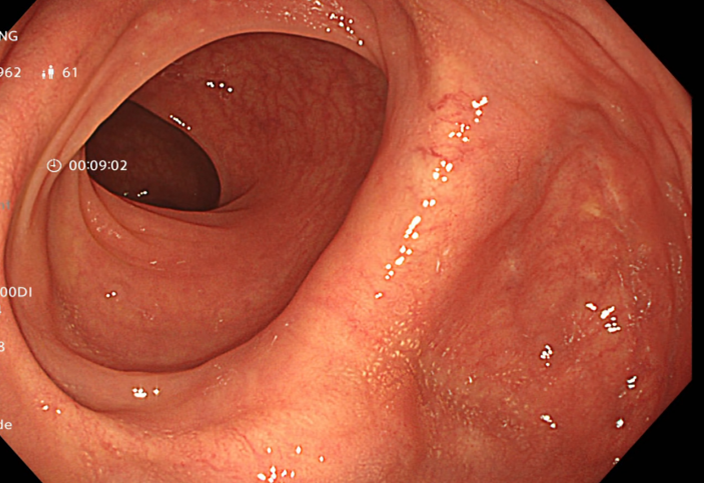

Kết quả nội soi dạ dày: Viêm teo niêm mạc dạ dày (C2 theo Kimura), dị sản ruột và có vi khuẩn H.pylori dương tính với test Urease từ mảnh sinh thiết qua nội soi.

Hình 1: Hình ảnh nội soi dạ dày